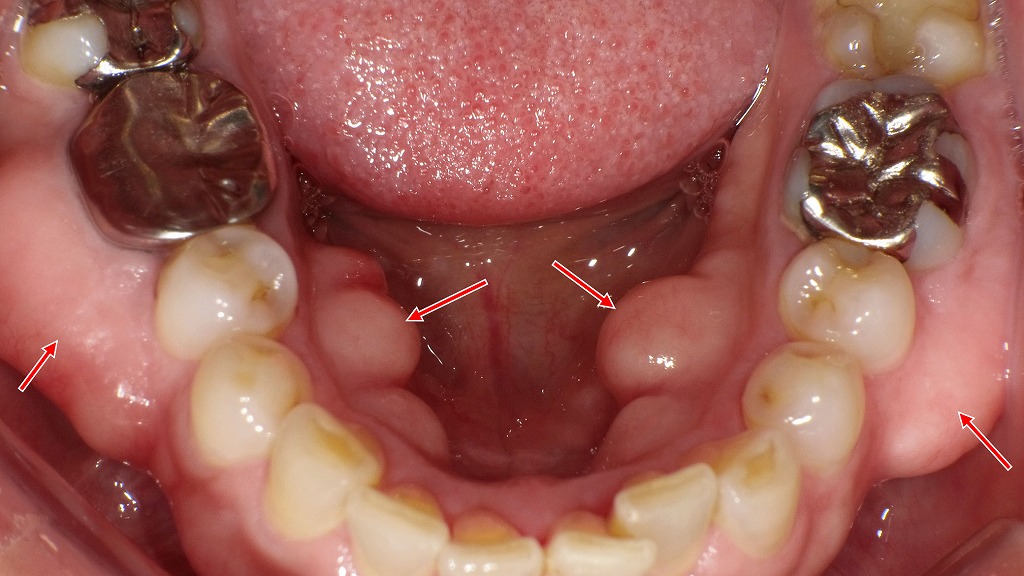

⑤ 骨隆起

下顎隆起(外骨症)

下顎骨の犬歯から小臼歯の内側の歯茎が腫れるように隆起します。下顎隆起は炎症によるものではないので痛みは起こりません。また、膿が出ることもありません。

外骨症は、骨が局所的に過剰発達することで生じる良性の骨隆起です。多くは下顎舌側(下顎隆起)にみられますが、まれに下顎頬側にも発生することがあります。噛みしめや歯ぎしりなどの慢性的な力が関与すると考えられており、通常は無症状です。ただし、舌や頬への違和感、清掃性の低下、入れ歯や補綴治療の支障となる場合には、経過観察や外科的対応が検討されます。